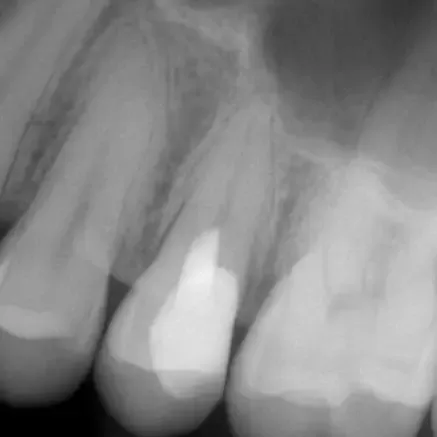

Röntgenbild: Instrumentenfragment Kontrolle nach Wurzelfüllung

Kontrolle nach Wurzelfüllung